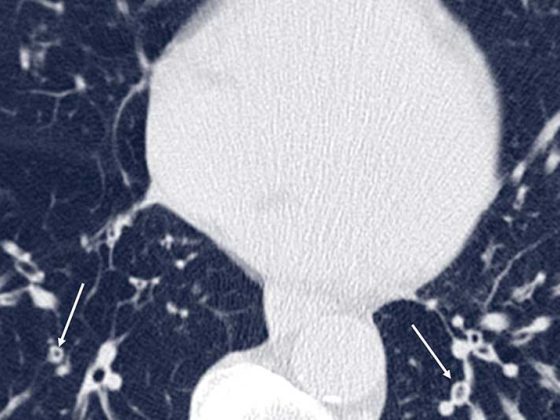

• Bildgebung bei der exazerbierten COPD

Infektexazerbierte COPD: Bildgebung zur Diagnostik und Risikobewertung